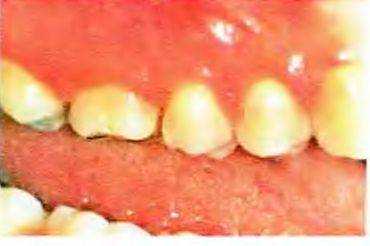

Рис. 5-53. Первый премоляр и первый моляр верхней челюсти, пораженные пародонтитом, препарированы под трехчетвертные опорные коронки по модифицированной методике. Планируется изготовление мостовидного протеза для замещения отсутствующего второго премоляра.

Рис. 5-54. Гипсовая модель верхней челюсти Хорошо видны две коробчатые полости на премоляре и комбинация медиальной коробчатой полости и нескольких проточек на первом моляре

Рис. 5-55. Мостовидный протез с опорой на модифицированные трехчетвертные коронки Видна степень рецессии десны у опорных зубов. В данном случае использование полных металлокерамических коронок было бы слишком разрушительно для твердых тканей зубов После разъяснения пациентке возможных вариантов лечения она предпочла частичные коронки. Незначительный объем металла, видимый с щечной поверхности, она сочла приемлемым.